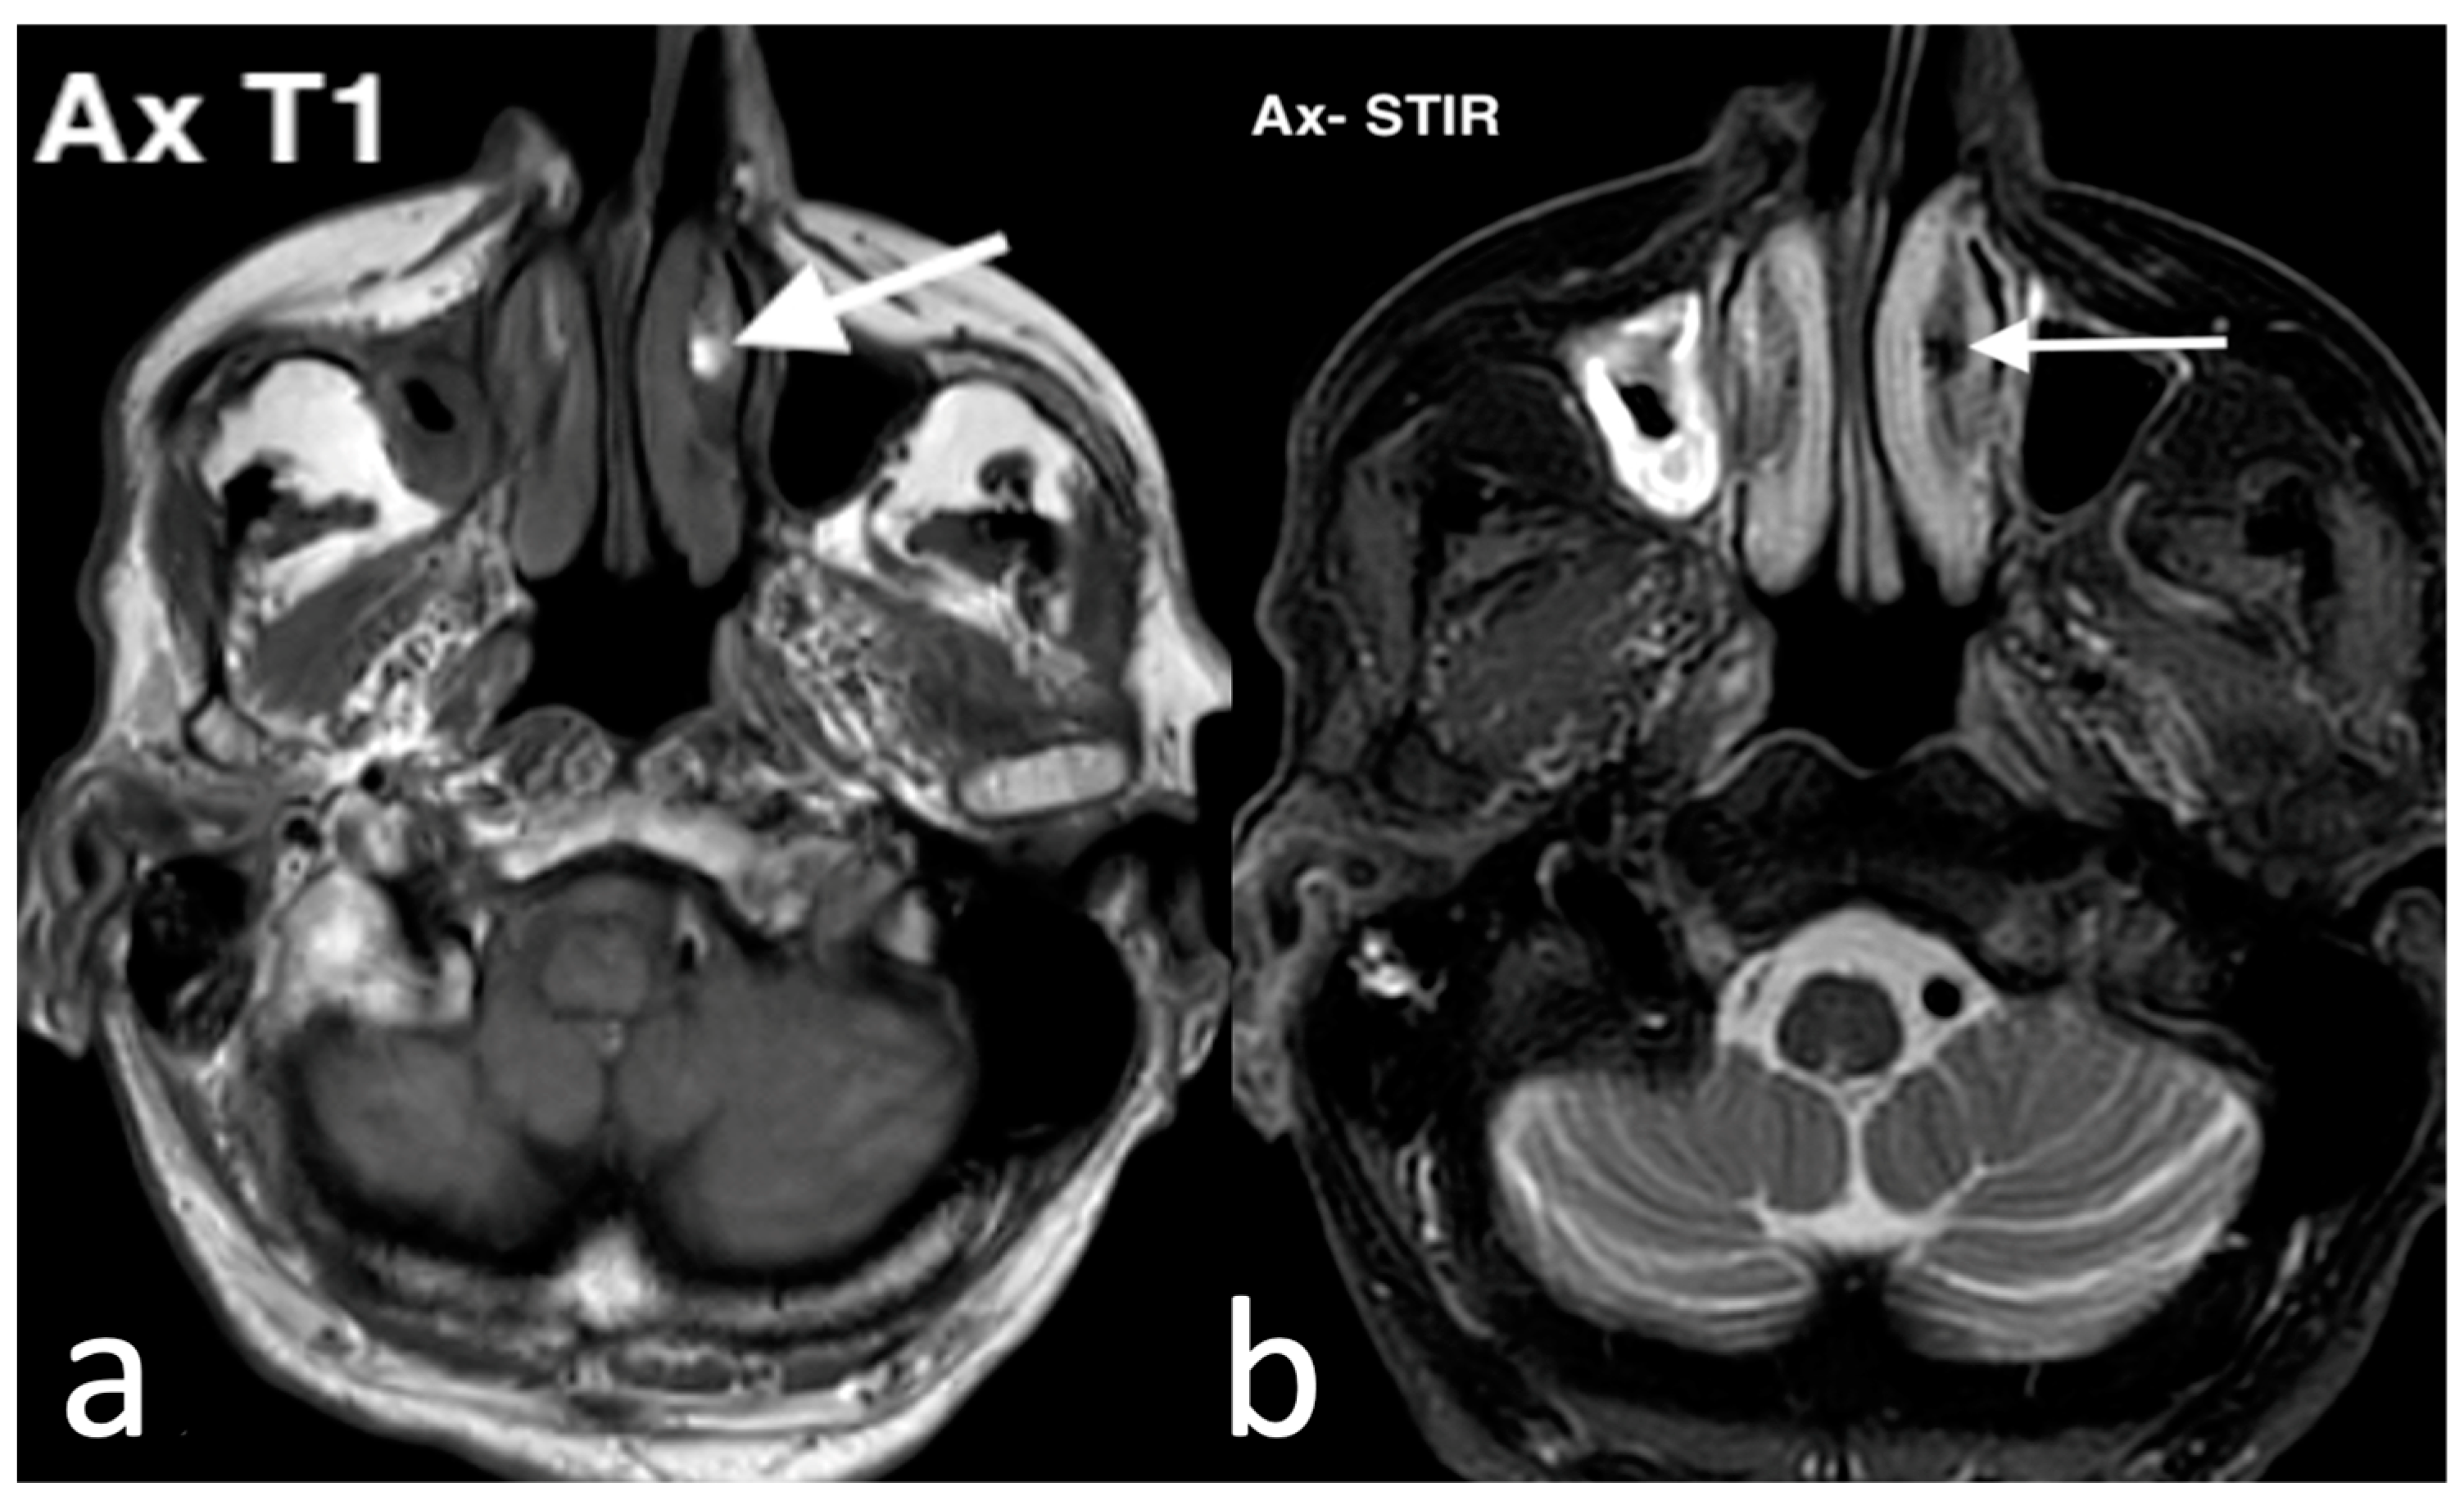

3.3.4. Melanoma

3.3.5. Rhabdomyosarcomas